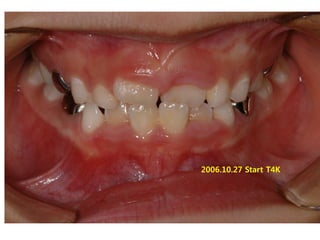

2006.09.07

2006.10.27 Start T4K

2007.02.02 4m

2008.01.1

3 1y 3m